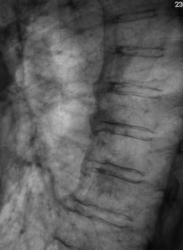

Пациентка направлена в рентгеновский кабинет врачом терапевтом для рентгенографии органов грудной полости. Пациентка предъявляет жалобы на наличие "сухого" кашля, субфебрильную температуру.

Произведена рентгенография в стандартных проекциях, томография в левой боковой проекции.

Похоже на метастазы.

Может я выдумываю, но не нравятся эти округлые тени, вероятно - метастазы.